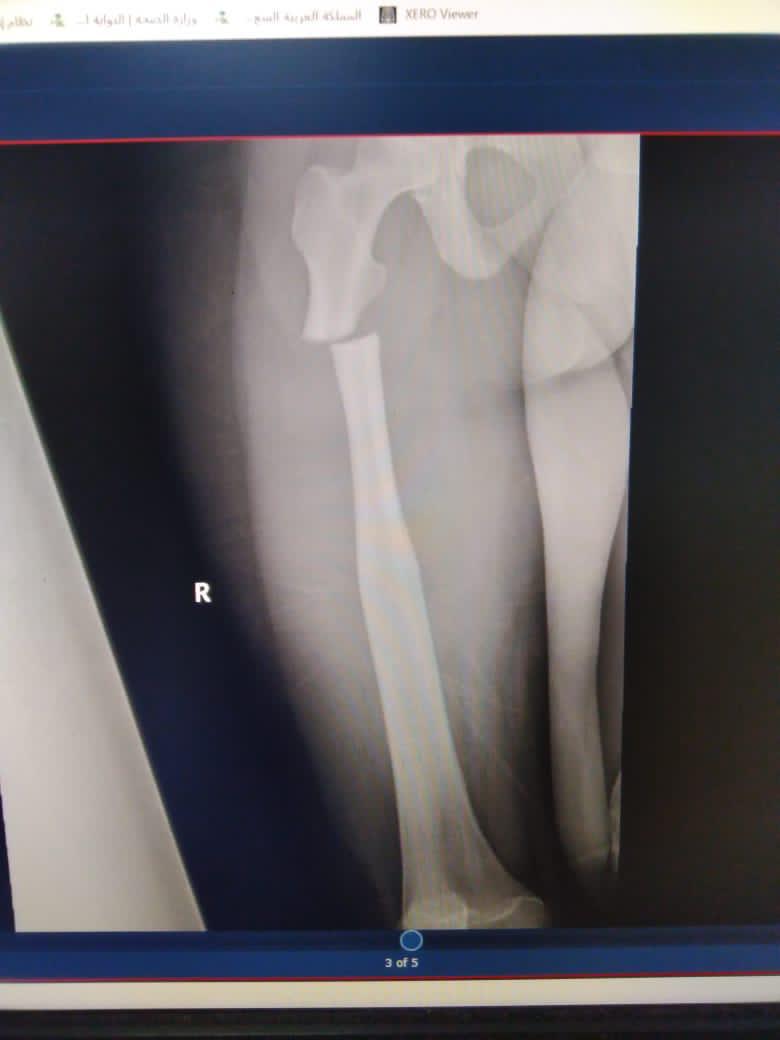

وتفصيلاً استقبل المستشفى شاب وفتاة في الخامسة عشرة من العمر ، يعانيّان من مرض نادر جدا في العظم يصيب واحدا من كل مائتين وخمسين ألفا وهو تصخر العظم (العظم الرخامي)، حيث يكون العظم صلبا كالصخر وبنيته البيولوجية مختلة قابلة للتكسر بسهولة، أضافة لعدم وجود قناة نخاعية داخل العظم ، و لا توجد توصيات علمية عالمية ثابتة للتعامل مع هذه الكسور لصعوبة الإجراءات التقنية بل واستحالتها، ناهيك عن المخاطر الجمة التي قد تتمخض عن أي وسيلة جراحية للتثبيت.